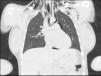

A previously healthy 21-year-old woman primigravida at 36 weeks of pregnancy underwent vaginal delivery of a male infant. In the inmediate pospartum period, she developed subcutaneous emphysema and chest discomfort. A chest X-ray (Fig. 1) revealed subcutaneous emphysema and signs of pneumomediastinum, including Naclerio's V (blue area) and the continuous diaphragm sign (yellow lines). She was treated with conventional oxygen therapy and analgesics. A non-contrast chest CT (Fig. 2) confirmed the presence of pneumomediastinum. During her hospital stay, she was managed conservatively, with gradual improvement of symptoms and resolution of the subcutaneous emphysema. As there were no signs of recurrence, she was discharged after five days.